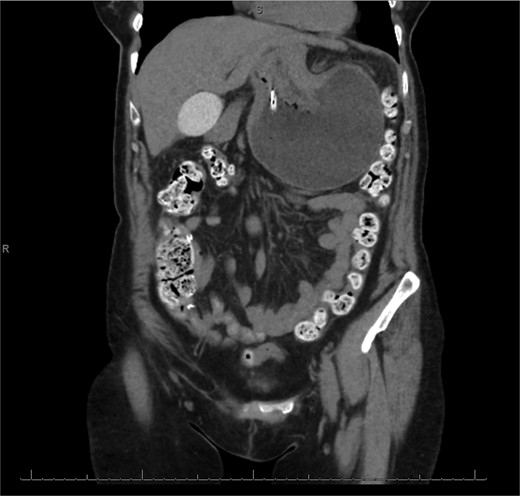

The patient was a 74-year-old female with a history of hypertension, chronic migraines, hiatal hernia repair with Nissen fundoplication repair, and cecal volvulus treated with right hemicolectomy who presented with abdominal pain, nausea, and vomiting. Six months prior, she exhibited symptoms of bloating and nausea, which were treated with oral Reglan with some improvement. She reported vomiting episodes for 2 months that acutely worsened over the 4 days prior to presentation. Examination revealed a soft and mildly distended abdomen with tenderness in the epigastrium and left upper quadrant. Initial vital signs showed a temperature of 36.1°C, blood pressure of 149/88 mmHg, heart rate of 115 beats/min, and oxygen saturation of 95% on room air; tachycardia resolved with resuscitation. Labs were notable for a white blood cell count of 8.8 × 1000/mcL and hemoglobin of 14.2 g/dL. Sodium was 137 mEq/L, potassium was 3.3 mEq/L, and creatinine was 0.75 mg/dL. Computed tomography (CT) of the abdomen and pelvis (Figs 1 and 2) showed gastric volvulus without pneumatosis, significant wall thickening, or distention. Nasogastric tube was placed. An upper gastrointestinal fluoroscopy scan showed no passage of contrast beyond the stomach and demonstrated 90° rotation of the stomach (see Fig. 3). The patient underwent surgery that same day.

Coronal view of CT scan of abdomen and pelvis demonstrating gastric volvulus.